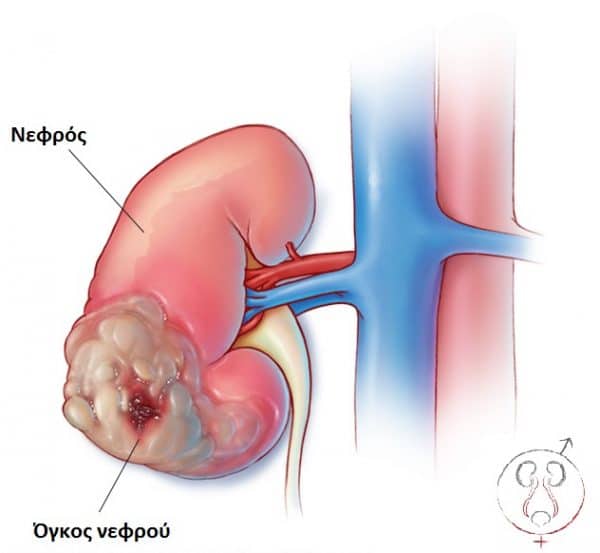

Ο καρκίνος των νεφρών εμφανίζεται όταν σχηματίζονται καρκινικά κύτταρα στα νεφρά. Πάνω από το 90% των καρκίνων των νεφρών είναι καρκινώματα των νεφρικών κυττάρων (RCC), τα οποία ξεκινούν από τα σωληνάρια των νεφρών. Τα σωληνάρια είναι μικροσκοπικοί σωλήνες στα νεφρά που βοηθούν στο φιλτράρισμα απορριμμάτων από το αίμα για να κάνουν ούρα. Το υπόλοιπο 10% των καρκίνων των νεφρών ξεκινά από τη νεφρική λεκάνη στο κέντρο του νεφρού, όπου συλλέγονται τα ούρα.

- Ένα από τα πρώτα συμπτώματα του καρκίνου των νεφρών είναι η εμφάνιση αίματος στα ούρα. Μερικές φορές, ένα κομμάτι μπορεί να γίνει αισθητό στην κοιλιά.